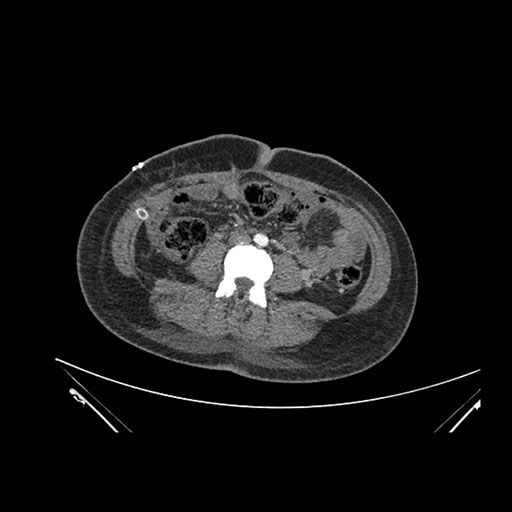

Imaging Analysis

Look through the patient's CT scan to identify any areas of concern for the necessary procedure.

Axial Arterial

Based on initial findings, which issue(s) would you be most concerned about?